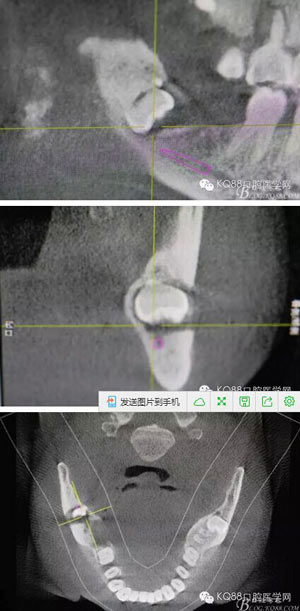

圖2.術(shù)前的CBC影像T檢查:48低位導(dǎo)致,近中牙尖緊鄰下頜神經(jīng)管。

2.jpg

圖3.其他方向的影像檢查:48近中牙冠與下頜管之間無(wú)骨壁相隔。

3.jpg

圖4.總體的CBCT影像:

4.jpg